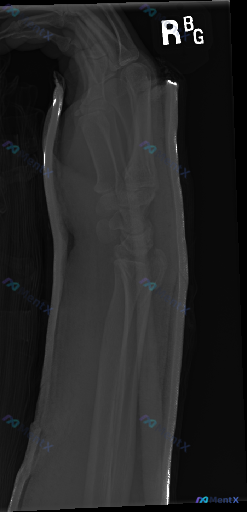

整理到一张右侧前臂侧位X光片的影像资料,大家可以先看看这些表现: 1. 桡骨远端骨干骺端可见骨皮质中断,骨折线通过,伴有背侧成角移位及粉碎性改变 2. 尺骨茎突也有骨皮质中断 3. 腕关节背侧及掌侧有明显软组织肿胀 4. 肘关节对合关系良好,尺桡骨中段皮质连续 5. 骨质密度分布均匀,未见明显骨质溶...

整理到一份右侧腕关节急性创伤后的侧位X光影像分析资料,先和大家同步一下关键发现: - 骨骼方面:桡骨远端可见骨折线,累及关节面,骨折远端向背侧移位、背侧成角,掌倾角完全丧失;尺骨茎突基底部也有骨折线。 - 关节方面:桡腕关节对合关系改变,关节面不平整,有碎块;近排腕骨(如月骨)随桡骨向背侧移位,腕骨...